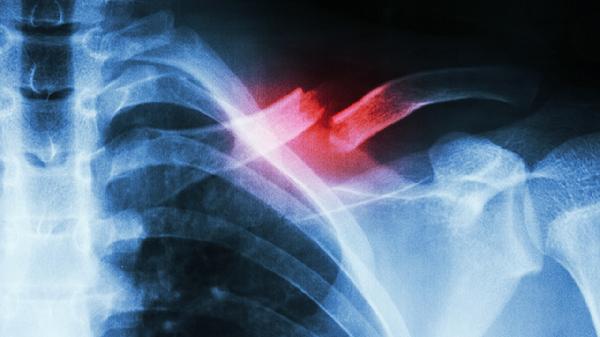

2、压痛

肋软骨炎患者在病变部位按压时会出现明显压痛,压痛点多位于肋软骨与胸骨连接处。压痛范围通常与炎症范围一致,可能伴随局部肌肉紧张。检查时需注意与肋骨骨折、胸膜炎等疾病鉴别。避免对压痛点过度按压或刺激,可尝试局部外用氟比洛芬凝胶贴膏或双氯芬酸二乙胺乳胶剂,同时配合休息减少胸廓活动。